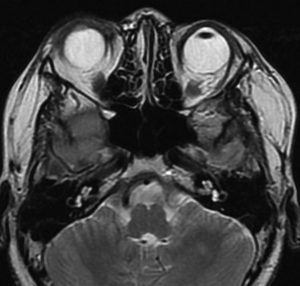

whole optic pathway pilocytic astrocytomaとは

両側の眼窩内視神経から視交叉、視索,外側膝状体,内包後脚,視放線近位部までが腫瘍化しています。FLAIRで高信号で,不規則にガドリニウム増強されます。これを手術摘出したり生検したりしても無駄です。放射線治療は不可能であり治療方法は化学療法のみです。

この子はCDDP/VCRの化学療法から開始して12年になりますが,今は無治療でわずかな視力ですが学校に通っています。優等生です。自然退縮を見ていますが,今後も変化する可能性はすこし残しています。